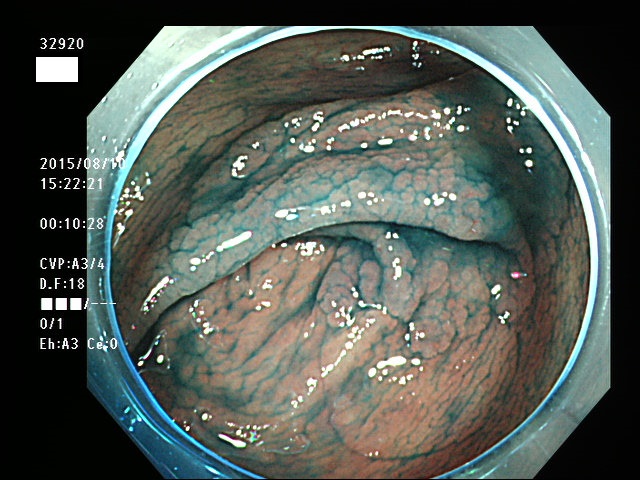

上記100名より抽出した平坦・陥凹型腺腫(=癌化の危険が高いが見落としやすい病変)の内視鏡写真

32901 32902 32903 32904 32905 32906 32907 32910 32911 32912 32915 32916 32918 32919 32920 32921 32922 32923 32924 32925 32926 32927 32928 32929 32931 32933 32935 32939 32941 32951 32953 32956 32957 32959 32961 32963 32964 32965 32967 32968 32971 32972 32973 32976 32978 32980 32981 32982 32986 32988 32989 32990 32994 32995 32998・・・・・・の55名